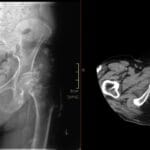

- Radiology Cases: Images with a to-the-point discussion highlighting the specific diagnostic criteria.

- Radiology Case of the Day Collection: Aunt-Minnie Board Cases for Rapid Review.

- Radiology Spotters: 700+ spot / “Aunt-Minnie” cases divided into sets of 10 each!